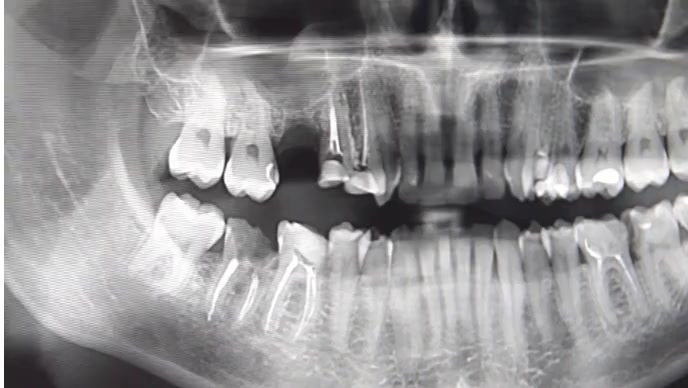

Rontgen gigi adalah pemeriksaan penunjang menggunakan sinar X untuk melihat kondisi bagian dalam gigi, akar gigi, tulang rahang, dan jaringan di sekitarnya. Pemeriksaan ini membantu dokter gigi mendapatkan gambaran yang lebih detail dan akurat sebelum menentukan tindakan.

Gigi berlubang kecil, infeksi akar, gigi impaksi, hingga kista sering tidak terlihat saat pemeriksaan biasa. - Menentukan Diagnosis yang Lebih Akurat